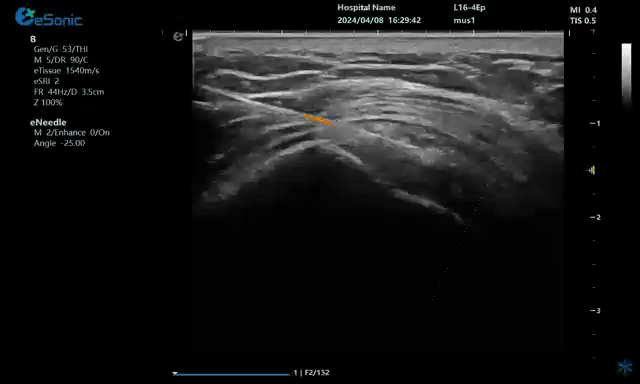

病例:冈上肌肌腱钙化穿刺治疗

640.gif

注射麻醉药

640 (1).gif

注射药物

640 (2).gif

无磁导航技术引导穿刺钙化点

钙化物.jpg

取出的钙化物